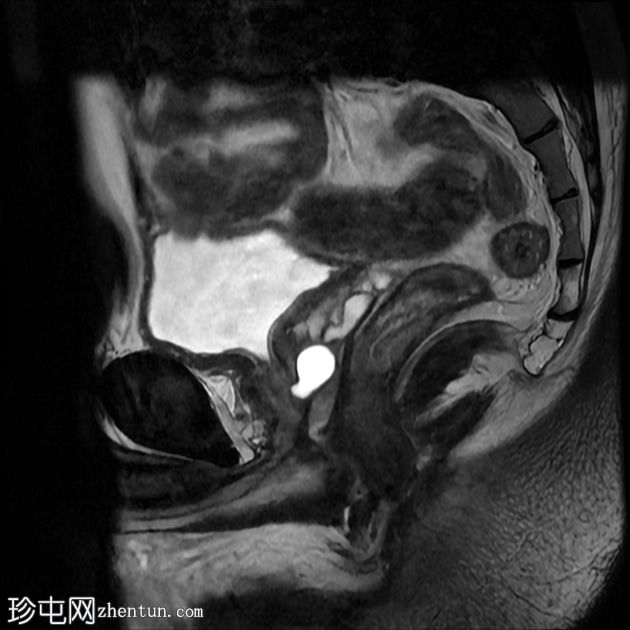

MRI

矢状位

T2加权像

前列腺大小为32.8 x 41.5 x 34.7 mm(前后径 x 宽度 x 头尾径),体积为25.88 ml,属于正常范围。前列腺中央可见一逗号状囊性占位性病变,大小为17.3 x 12.1 x 9.3 mm(头尾径 x 前后径 x 宽度)。可见囊肿与前列腺尿道相通。囊内未见可疑内容物——具体而言,未见囊内出血或碎屑——弥散加权成像结果为阴性,提示无囊内感染。

动态增强扫描显示前列腺呈均匀强化,未见可疑的周边部或移行区异常。精囊正常。膀胱正常。盆腔内未见可疑淋巴结。

本例为一例发生于青年人的单纯性逗号状中央型前列腺内囊肿。

根据囊肿位于前列腺中央或中线(精阜水平)、患者年龄(二十岁左右)以及无前列腺外延伸和明显的尿道交通,前列腺囊肿是首选诊断。苗勒氏管囊肿通常难以排除。患者的年龄、无前列腺外延伸以及疑似尿道交通使该诊断的可能性降低。